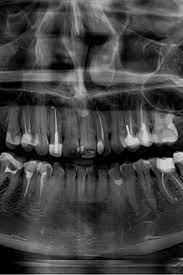

Ортопантомограма (ОПТГ) потрібен щоб:

• Оцінити стан зубів, коріння, каналів. А також побачити пломби, імпланти, коронки, проаналізувати структуру тканин пародонту.

• Виявити приховані запальні процеси, каріозні порожнини, патологічні утворення (кісту, абсцес).

• Виявити пародонтальні кишені.

• Провести оцінку стану навколозубних тканин, верхньощелепних синусів, скронево-щелепного суглоба.

• Визначити параметри щелепної кістки, положення, стан зубів у ряду, включаючи зуби мудрості.

Ортопантомограма — це швидше допоміжний діагностичний інструмент, що надає оглядову картину і виявляє явну патологію. На відміну від панорамного знімка, 3D комп’ютерна томографія дає не одне плоске зображення щелепи. Лікар отримує низку послідовних зображень у різній проекції без спотворень, властивих панорамного знімка. Отримане тривимірне зображення дозволяє лікарю розглянути щелепно-лицьову зону на будь-якій глибині з усіх боків та кутів. Приклад: на панорамному знімку видно правильний імплант, а на КТ дослідженні виявлені помилки при встановленні.